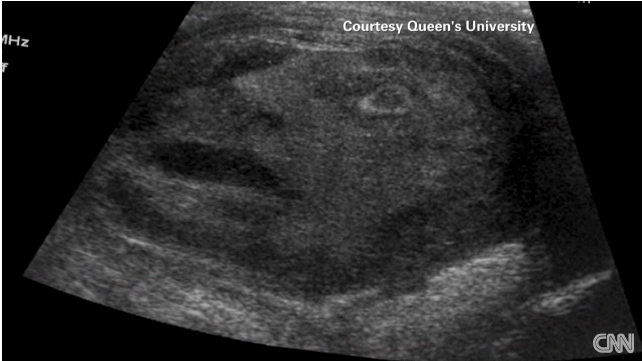

video Testicular tumor with a 'spooky face'